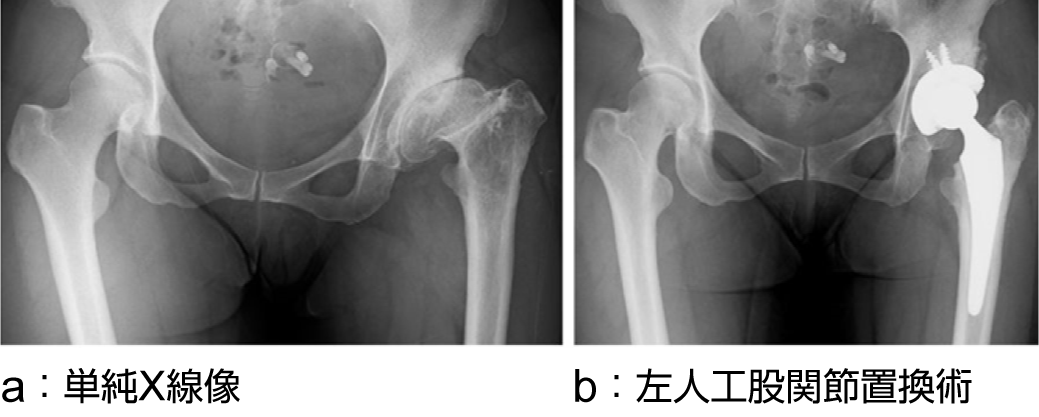

変形性股関節症

a:単純X線像

b:単純X線像 左人工股関節置換術後

出典

img

1: 著者提供